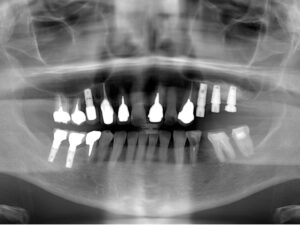

1.患者様の主訴:左上にインプラントを入れたい

2.診断結果:

左上の奥の骨の厚みが薄いため上顎洞を挙上する必要がある

3.治療内容:

上顎洞挙上術を行なって6ヶ月経過したのちにインプラントを入れた

写真は治療前骨の厚みが1mm以下だったところ、上顎洞挙上術で1cm程度の骨の厚みになり、9mmのインプラントを入れた。その後半年待ってから上部構造を入れた。

5.治療期間:1年

6.治療費用:

CT診断¥22,000+上顎洞挙上術¥165,000+臼歯インプラント440,000×3本=¥1,507,000

7.リスク・副作用:上顎洞粘膜の穿孔、術後の脹れ